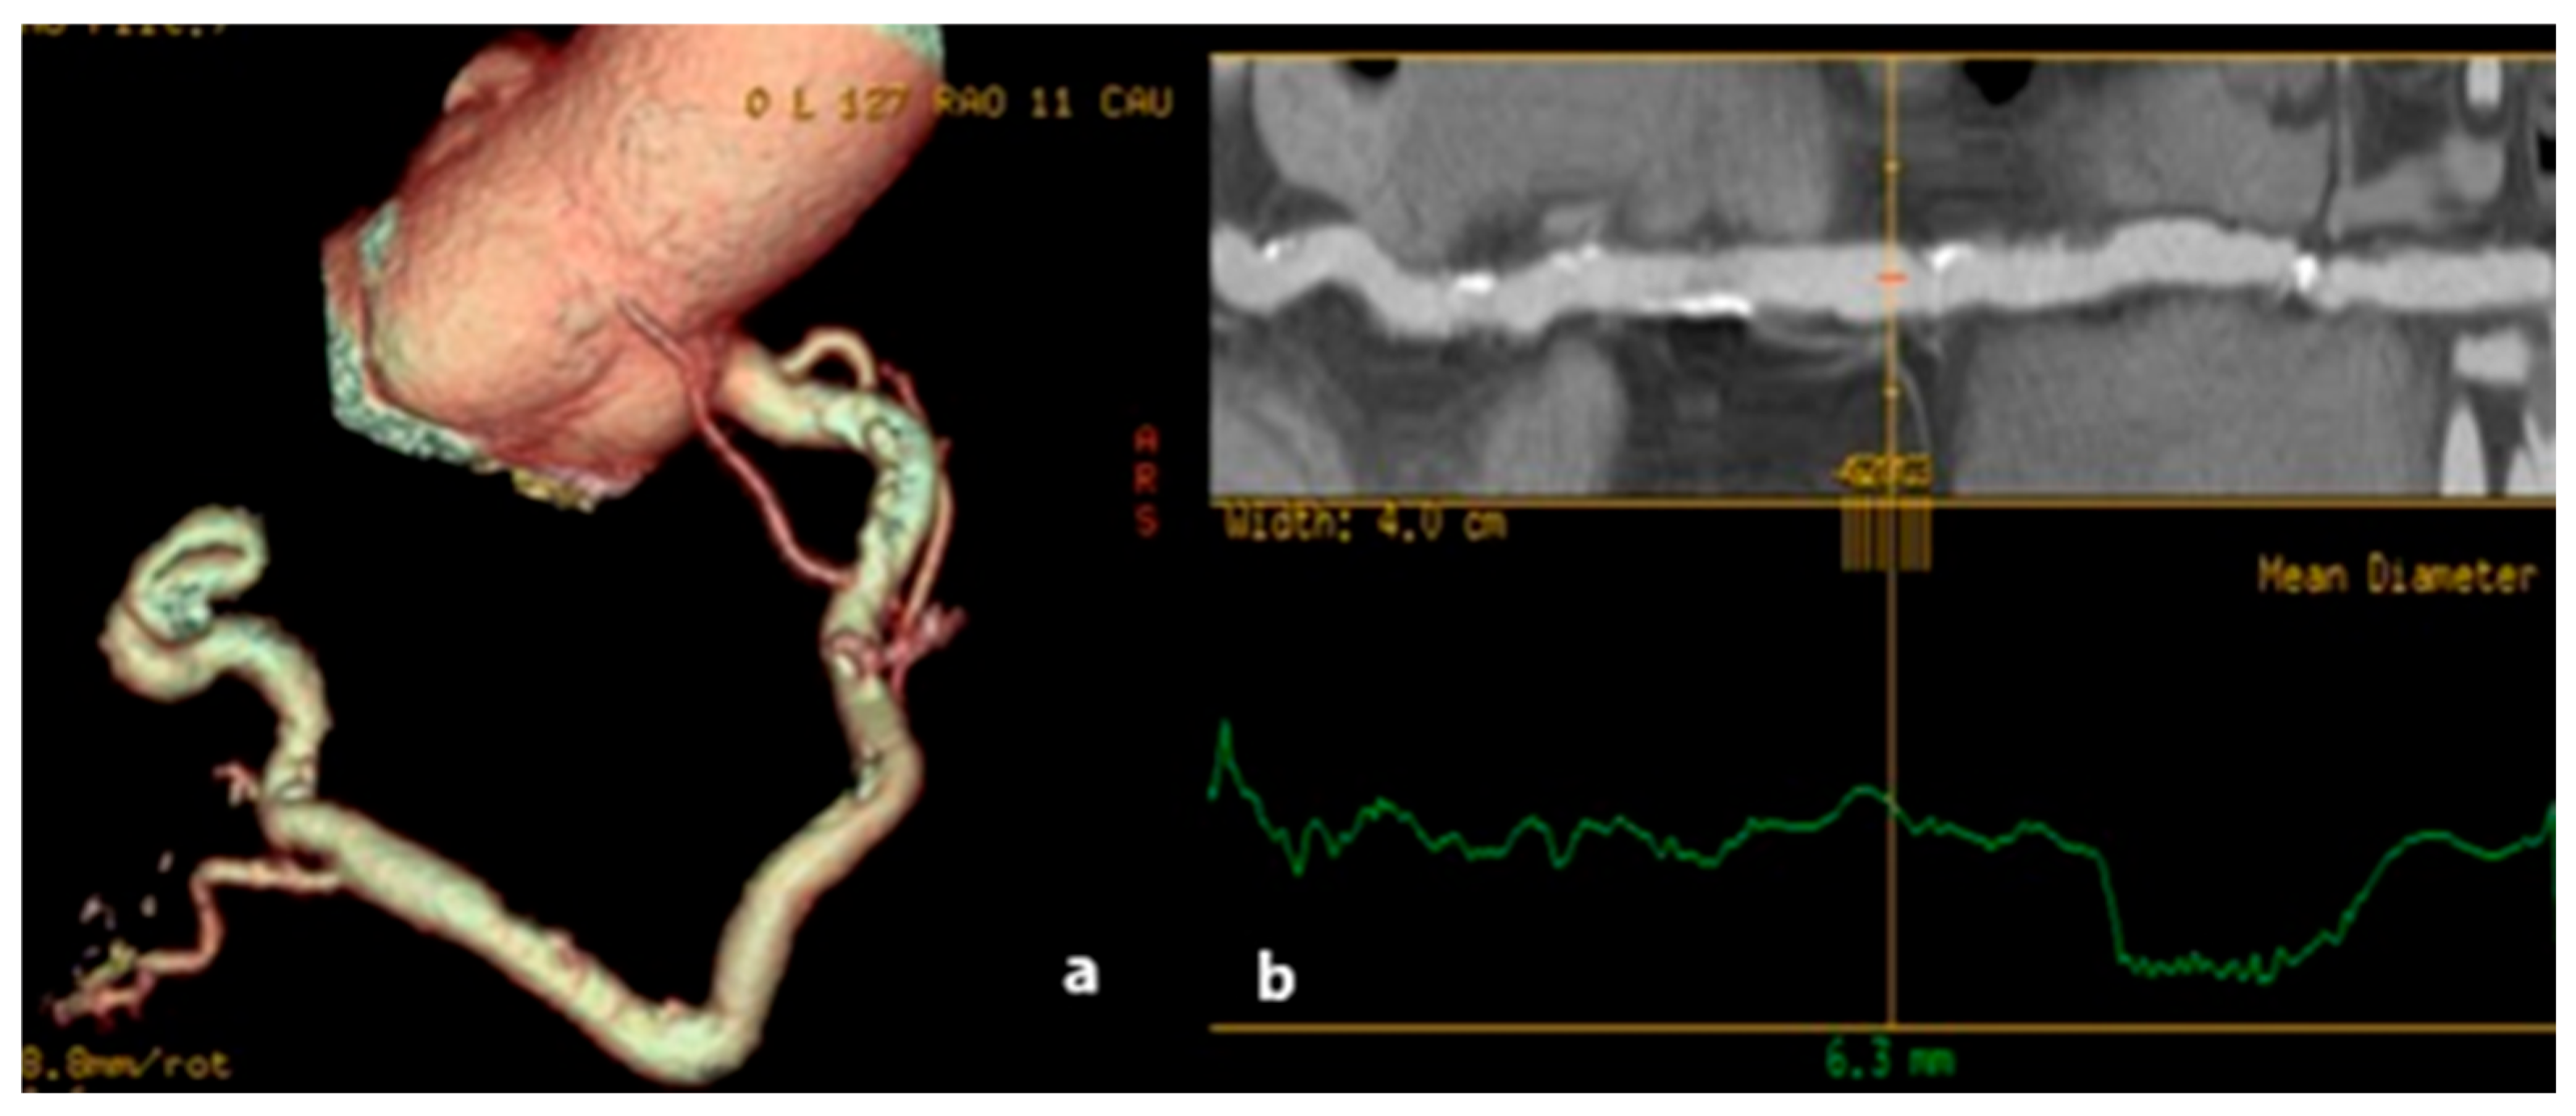

3.2. Pathological Dilatation of Coronary Arteries: Aneurysm and Ectasia